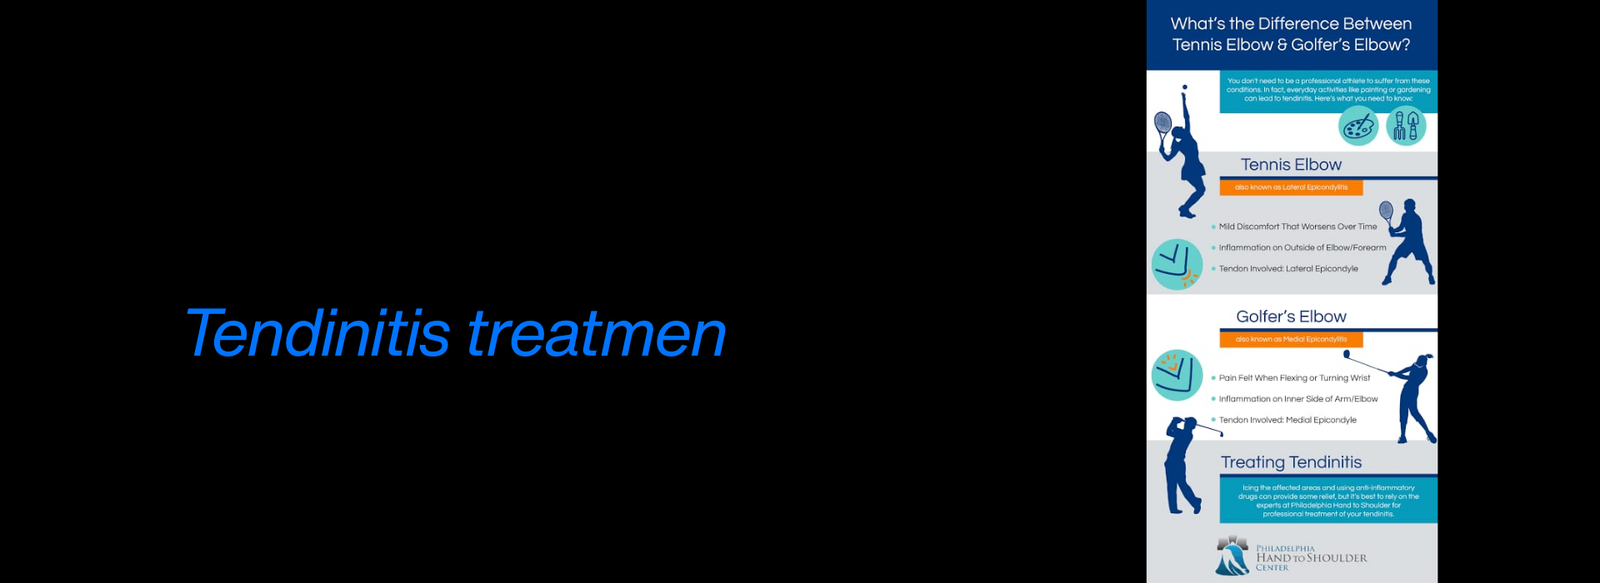

Fellowship in Arthroscopy: Expertise in minimally invasive surgery to diagnose and treat joint conditions, such as torn cartilage or ligament injuries, particularly of the knee, shoulder, and hip.